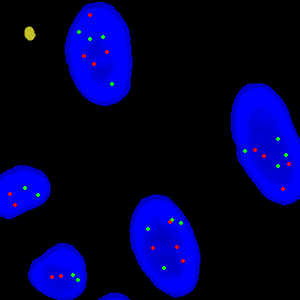

Figure 3

Close-up of a single nuclei with gene probes.

Figure 4

The same FOV as FIGURE 3, where the gene probes have been detected with a green and red cross.